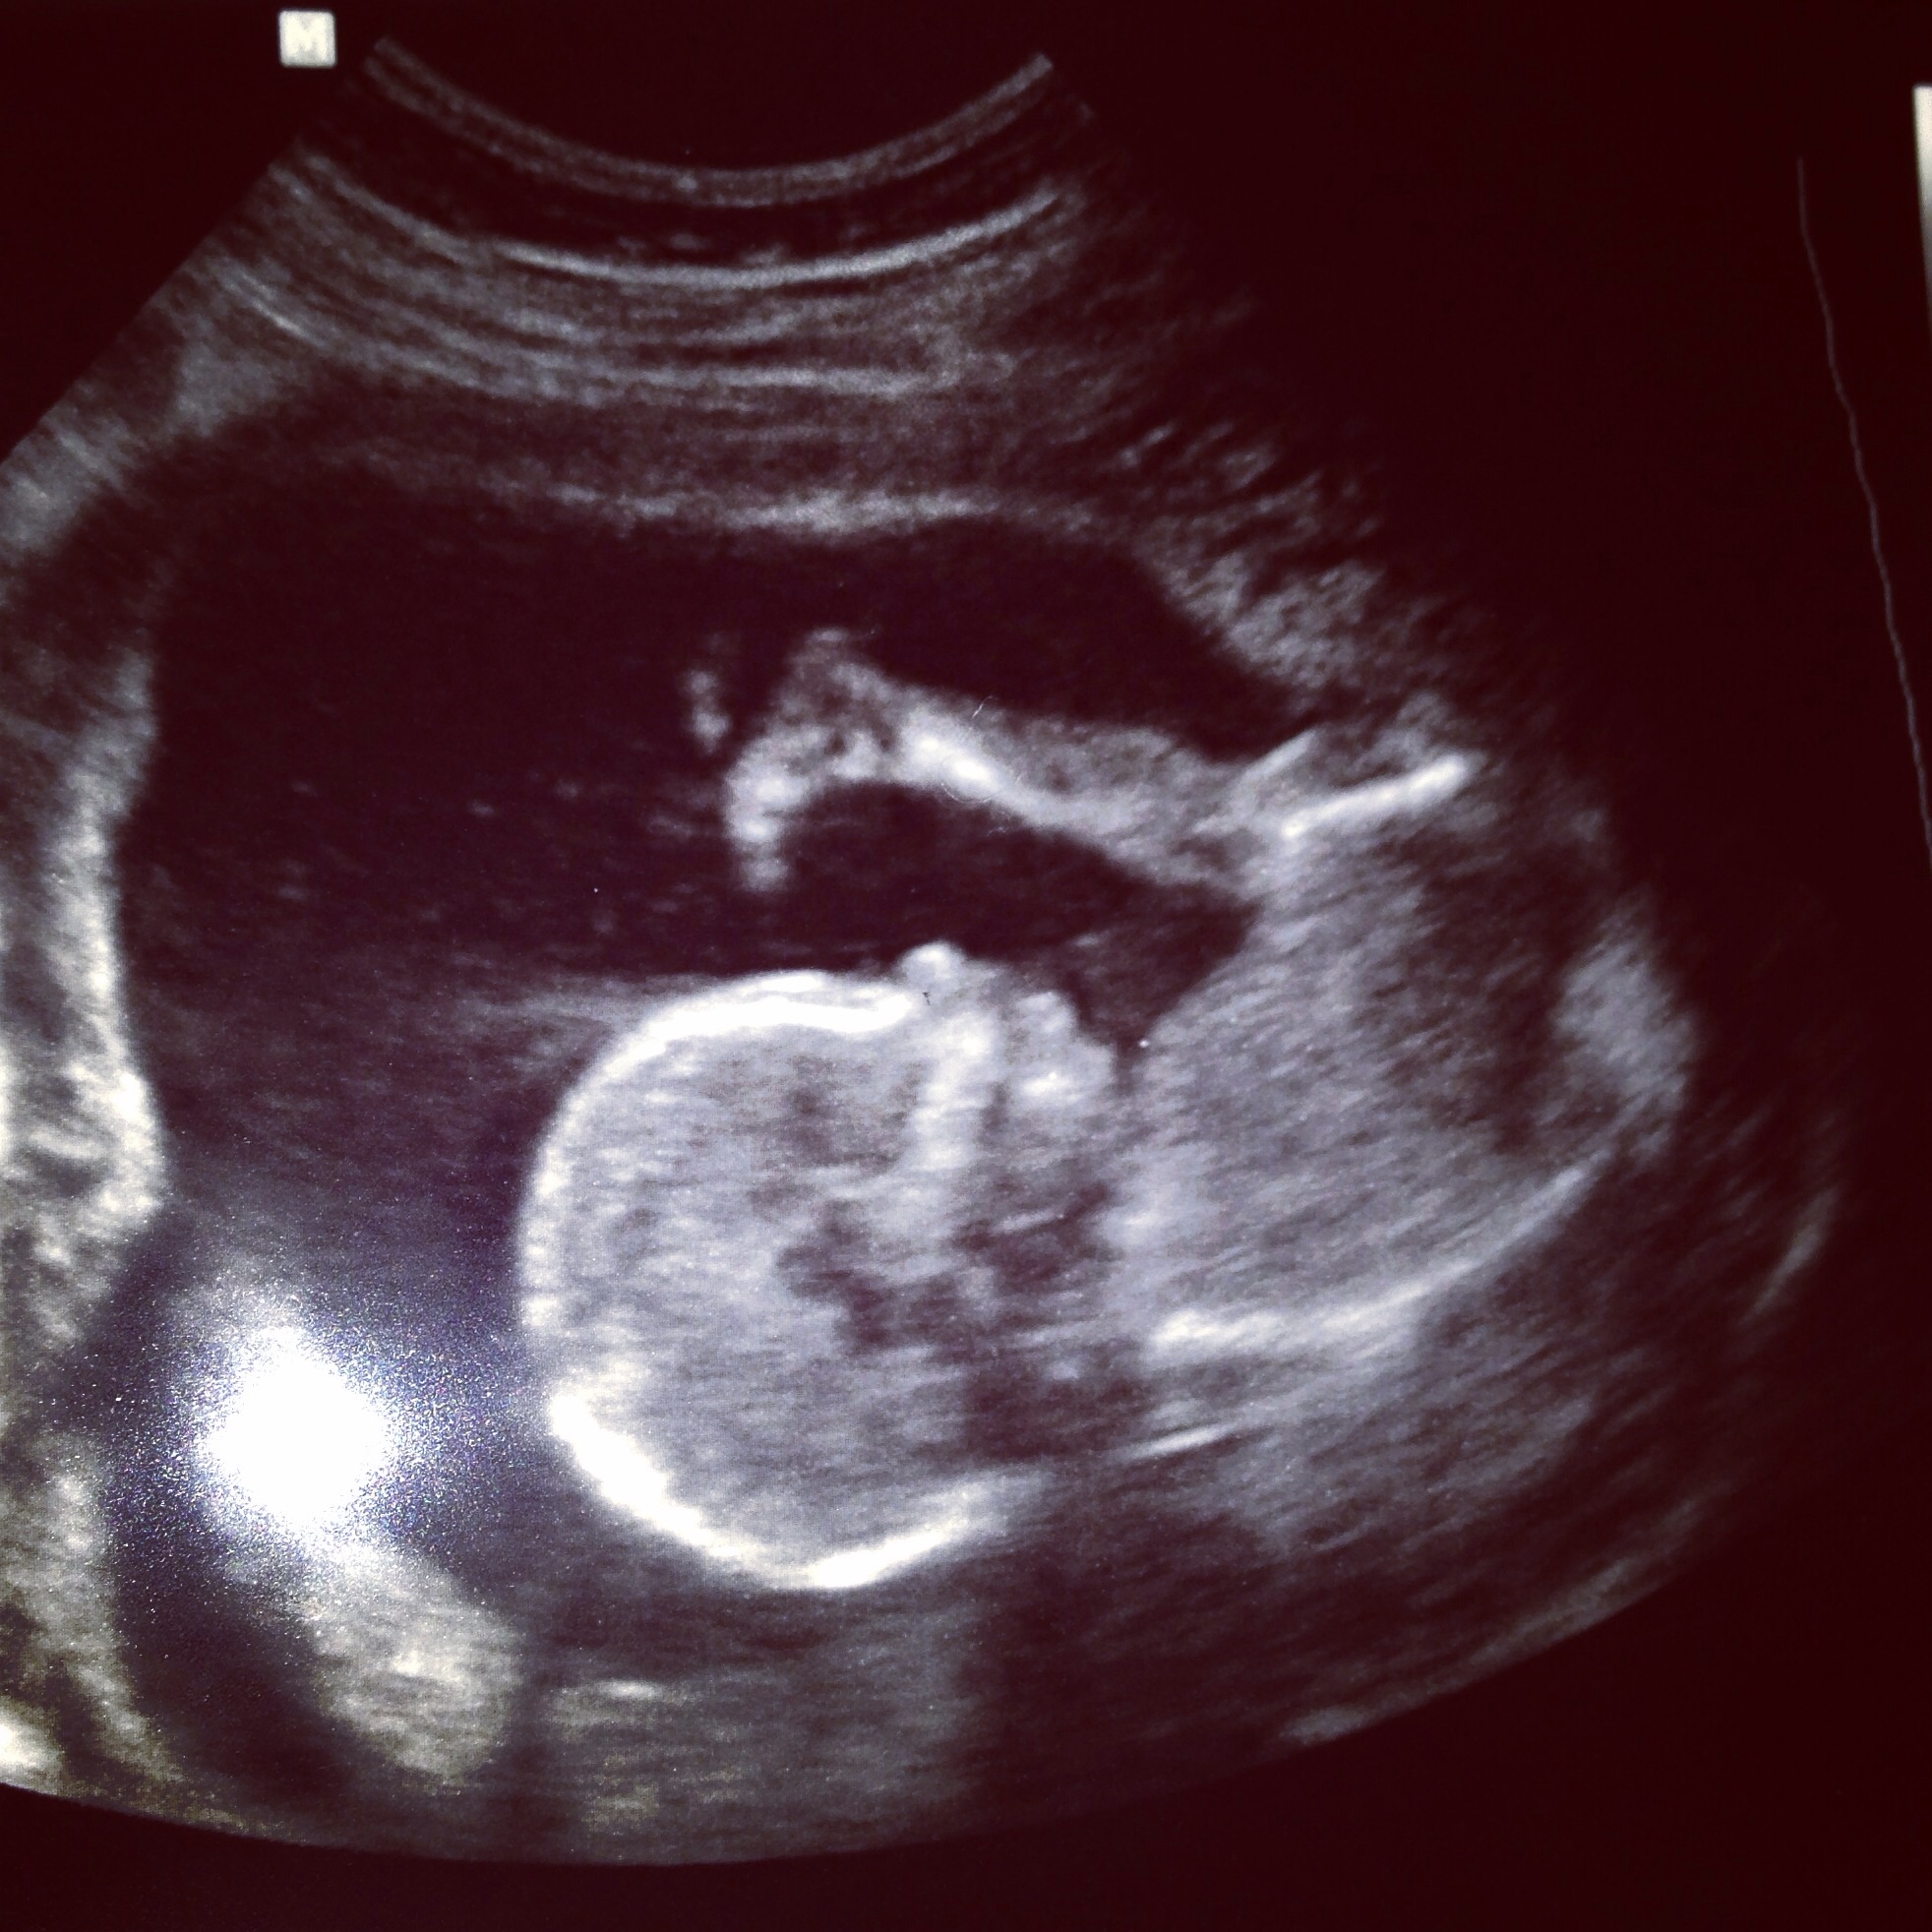

Appointments/updates: we had our elective gender scan last Monday and found out we're having a girl!!! (What we were hoping for) But we have our regular midwife check on Tuesdat and A/S on Friday of next week. We're gonna be spoiled hearing and seeing her so much.

Rants/raves-ready to feel this kiddo move! Rave, umm here's one of our ultrasound pics cause I'm a proud mom and forgot to post any when we found out . Our little gymnast lol, those be legs.